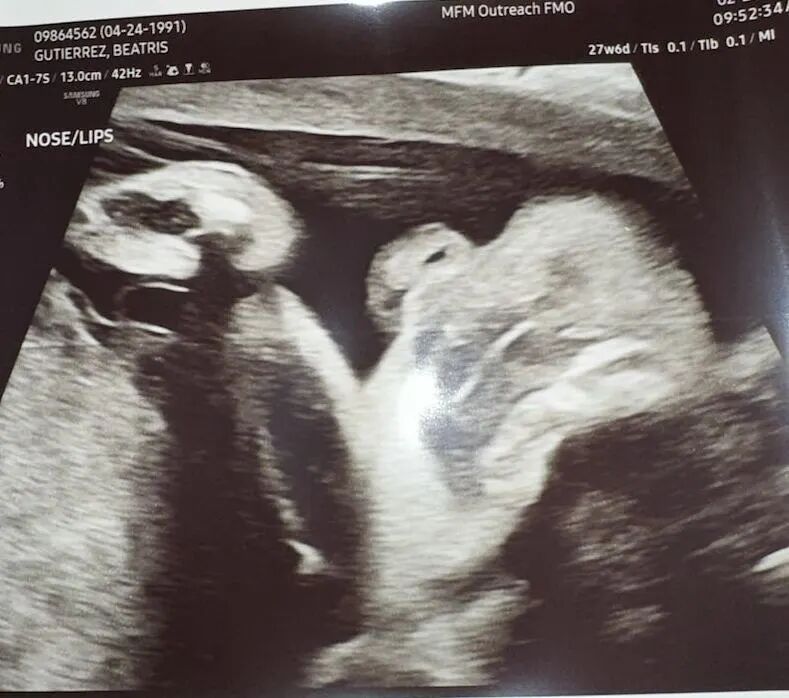

爱妈B已接近孕期的第37周,宝宝几乎已经准备好迎接这个世界。通过最近的B超,我们可以清楚地看到宝宝的面容,非常可爱。宝宝的体重约为6.5磅,身长在19到20英寸之间。他们的肺部和大多数重要器官已经发育成熟,准备在出生后立即发挥功能。尽管在子宫内的空间越来越小,宝宝的活动—如翻身或踢动—依然频繁,有时这些动作会给爱妈带来一些不适。